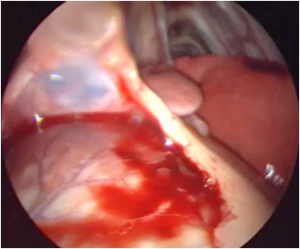

- 1 major complication in Group 2 case 2

- Pigtail loss, thoracoscopic reimplantation neededTwiddler syndrome